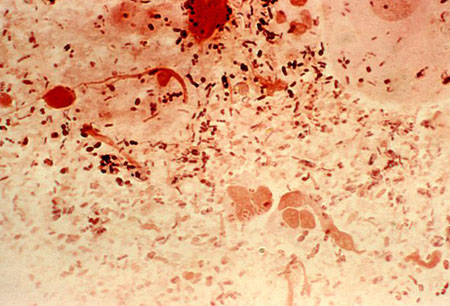

Assessment of proctitis

Gram stained photomicrograph of rectal smear revealing the presence of Gram-negative Neisseria gonorrhoeae

CDC/ Joe Miller